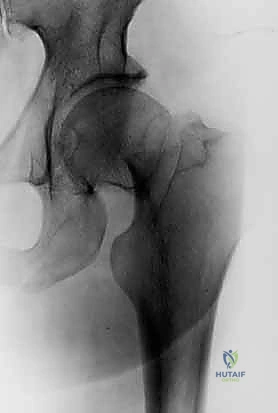

لفهم خطورة كسر عنق الفخذ وكيفية علاجه، يجب أن نبدأ بمراجعة الجوانب الأساسية لتشريح عنق الفخذ ومفصل الورك. مفصل الورك هو مفصل كروي حُقي (Ball-and-Socket Joint)، يتكون من رأس الفخذ (الكرة) والتجويف الحُقي في الحوض (المقبس). عنق الفخذ هو الجسر العظمي الذي يربط رأس الفخذ بجسم العظمة (Shaft).

عند النظر إلى الشكل الطبيعي لرأس وعنق الفخذ في الصور الشعاعية الأمامية الخلفية (AP) والجانبية، نلاحظ منحنى S لطيفًا مميزًا. هذا الشكل الانسيابي والمتماثل على الأسطح العلوية والسفلية والأمامية والخلفية ليس عشوائيًا، بل هو تصميم هندسي رباني لتوزيع الضغط والوزن. هذا المنحنى هو المعيار الذهبي الذي يعتمد عليه الجراحون المهرة، مثل الدكتور محمد هطيف، لتحديد الرد التشريحي الصحيح (Anatomical Reduction) أثناء الجراحة. أي خلل في استعادة هذا المنحنى يؤدي إلى توزيع غير متكافئ للوزن، مما يزيد من احتمالية فشل التثبيت أو حدوث خشونة مبكرة في المفصل.

2. التروية الدموية (Blood Supply): نقطة الضعف القاتلة

يُعد الإمداد الدموي لعنق الفخذ ورأسه أمرًا بالغ الأهمية لفهم المخاطر المرتبطة بهذه الإصابات. تعتمد الأوعية الدموية للفخذ القريب بشكل أساسي على الشريان الفخذي المنعطف الإنسي (Medial Femoral Circumflex Artery - MFCA)، وتحديدًا فرعه الخلفي، الذي يغذي الشرايين الشبكية (Retinacular Vessels of Weitbrecht).

تصعد هذه الشرايين الشبكية على طول سطح عنق الفخذ من الخارج لتوفير تدفق دم رجعي (Retrograde Flow) إلى رأس الفخذ. هناك مساهمات طفيفة ومتغيرة من شريان الرباط المدور (Artery of Ligamentum Teres)، الذي ينشأ من الشريان السدادي، ولكنه غالبًا لا يكفي وحده لتغذية رأس الفخذ لدى البالغين.

هذا الانقطاع في التروية الدموية هو السبب الرئيسي لارتفاع معدل حدوث النخر اللاوعائي (Avascular Necrosis - AVN) لرأس الفخذ، والذي يحدث في حوالي 15% إلى 30% من الحالات، بالإضافة إلى خطر عدم الالتئام (Non-union)، خاصة في الكسور المزاحة بشكل كبير.

لا تُعالج جميع كسور عنق الفخذ بنفس الطريقة. يعتمد الأستاذ الدكتور محمد هطيف على أنظمة تصنيف عالمية دقيقة لتحديد مدى خطورة الكسر واختيار التدخل الجراحي الأمثل. أهم هذه التصنيفات هو تصنيف جاردن (Garden Classification)، والذي يعتمد على مدى إزاحة (تحرك) العظم المكسور بناءً على صور الأشعة السينية.

يُعد درجة الإزاحة العامل الأكثر أهمية الذي يؤثر على قرارات العلاج. الكسور غير المزاحة (جاردن 1 و 2) تستجيب بشكل ممتاز للتثبيت عبر الجلد بالمسامير المجوفة. أما الكسور المزاحة (جاردن 3 و 4)، فتتطلب تقييماً دقيقاً لعمر المريض ومستوى نشاطه.

- الأشعة السينية (X-Rays): هي حجر الزاوية في التشخيص. يتم أخذ صور من زوايا متعددة (أمامي خلفي AP للورك والحوض، وصورة جانبية Cross-table lateral).